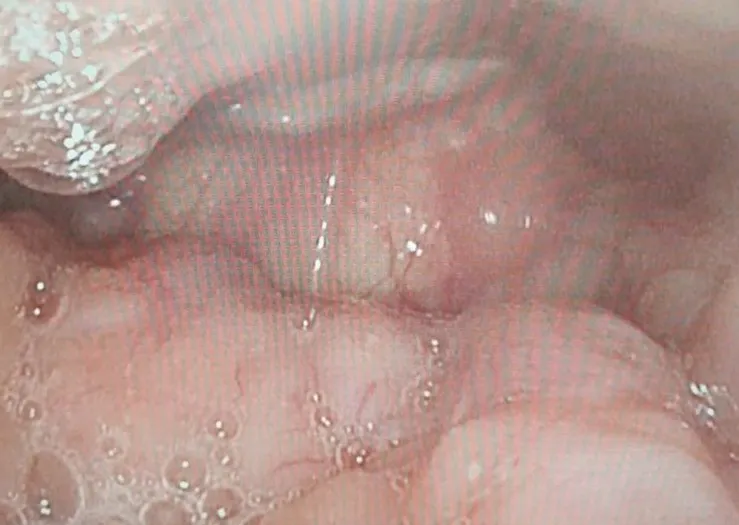

三軍總醫院以藥物誘導患者入睡,再由內視鏡經鼻腔往咽喉直接觀察,精確地找出每個患者的阻塞位置,邱逢翔指出,這可幫助醫師制定手術計畫,提高治療效果,避免過度破壞的併發症,造福許多睡眠呼吸中止症的患者。